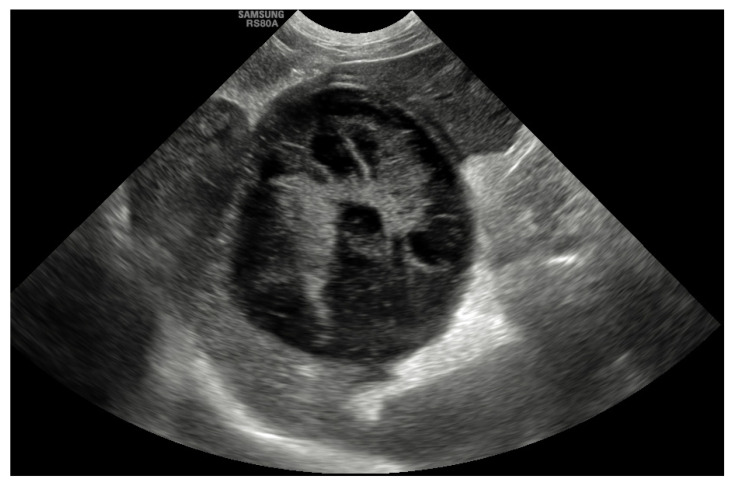

Abdominal ultrasound was the most common diagnostic tool used to diagnose GBM and was performed in all cases (100%). The most common abnormality that was described in 45 dogs (55%) was evidence of a GBM with a stellate or so-called “kiwi-fruit” pattern (Figure 1). A combination of a distended and thick gallbladder with hyperechoic and organized bile sediment compatible with an early GBM was described in the other 37 cases (45%). Hyperechoic pericholecystic fat was described in 11 dogs, and free peritoneal fluid was reported in 7 dogs. Other findings included hepatomegaly (15%), congenital extrahepatic portosystemic shunt (EHPSS; 2.5%), liver nodules (7%), splenic nodules (1.2%), bilateral adrenal gland enlargement (1.2%) and bladder nodules (1.2%). The common bile duct was considered to be within the normal limits (<4 mm) in 72 dogs (88%), mildly dilated (5–6 mm) in 8 dogs (10%) and moderately dilated (>7 mm) in 2 dogs (2.4%). The intrahepatic ducts were considered normal in all cases.